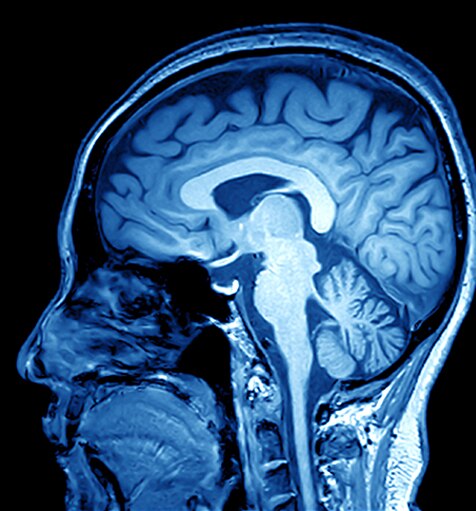

Die MRT (Magnetresonanztomographie) ist eine nicht-invasive Scan-Technologie, die Schnittaufnahmen des Körpers produziert. Sie kommt in einer Reihe von medizinischen Fachgebieten zum Einsatz, z. B.: Muskel-Skelett-Erkrankungen, Gastroenterologie, Onkologie, Herz- und Gefäßheilkunde und neurologische Bildgebung. MRT-Scans können Weichgewebestrukturen in beliebigen Ebenen differenzieren, was sie zu einem unverzichtbaren Diagnosewerkzeug macht.

MRT-Scanner erzeugen ein starkes Magnetfeld, das in Verbindung mit Hochfrequenzströmen verwendet wird, um spezifische Moleküle im Körper anzuregen.

Anhand des Verhaltens dieser Moleküle kann ein dreidimensionales Bild von Körpergewebe erzeugt werden. Beispiele für MRT-Bilder finden Sie nachstehend: